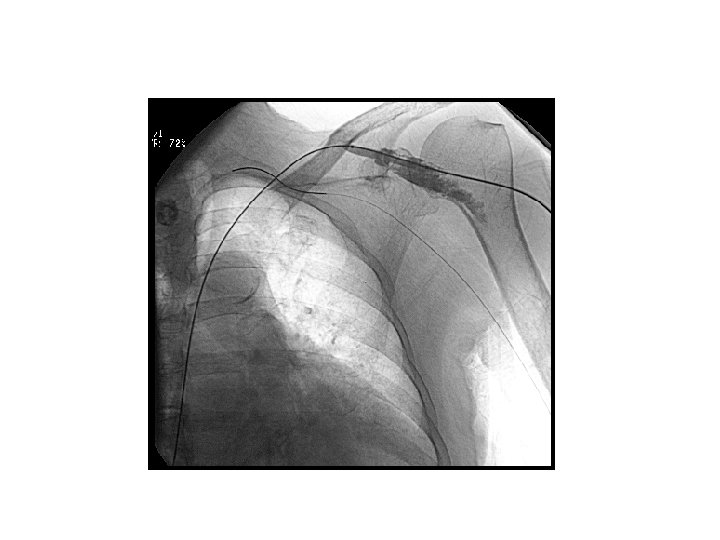

katater malpozisyonu • ideal lokalizasyon? (SVK, atriyokaval bileşke, sağ atriyum) • Primer / sekonder malpozisyon • Görüntüleme eşliğinde olmayan işlemlerde %3, 7 primer malpozisyon

katater malpozisyonu • IJV / SCV giriş – Azigos – Karşı brakiosefalik – İnferior vena kava – İnternal mamariyan ven • Femoral giriş – Asendan lomber dallar – Renal ven

katater malpozisyonu • Floroskopi eşliğinde düzeltme • Aynı aksesten yeni kateter takma • Farklı aksesten yeni kateter takma